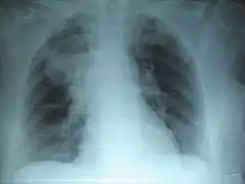

El Día Mundial de la Neumonía es una celebración anual que se lleva a cabo el 12 de noviembre desde 2009, fue establecido por la Coalición Global contra la Neumonía Infantil en ese mismo año.

El 12 de noviembre se celebra este día en todo el mundo. En 2019, la neumonía fue responsable de la muerte de 740 180 niños menores de cinco años. Esto a supuesto una mejora respecto a datos anteriores[6] que se debe a intervenciones como la vacunación, la mejora de la nutrición y la atención a los factores ambientales que aumentan la susceptibilidad a la enfermedad.[7]